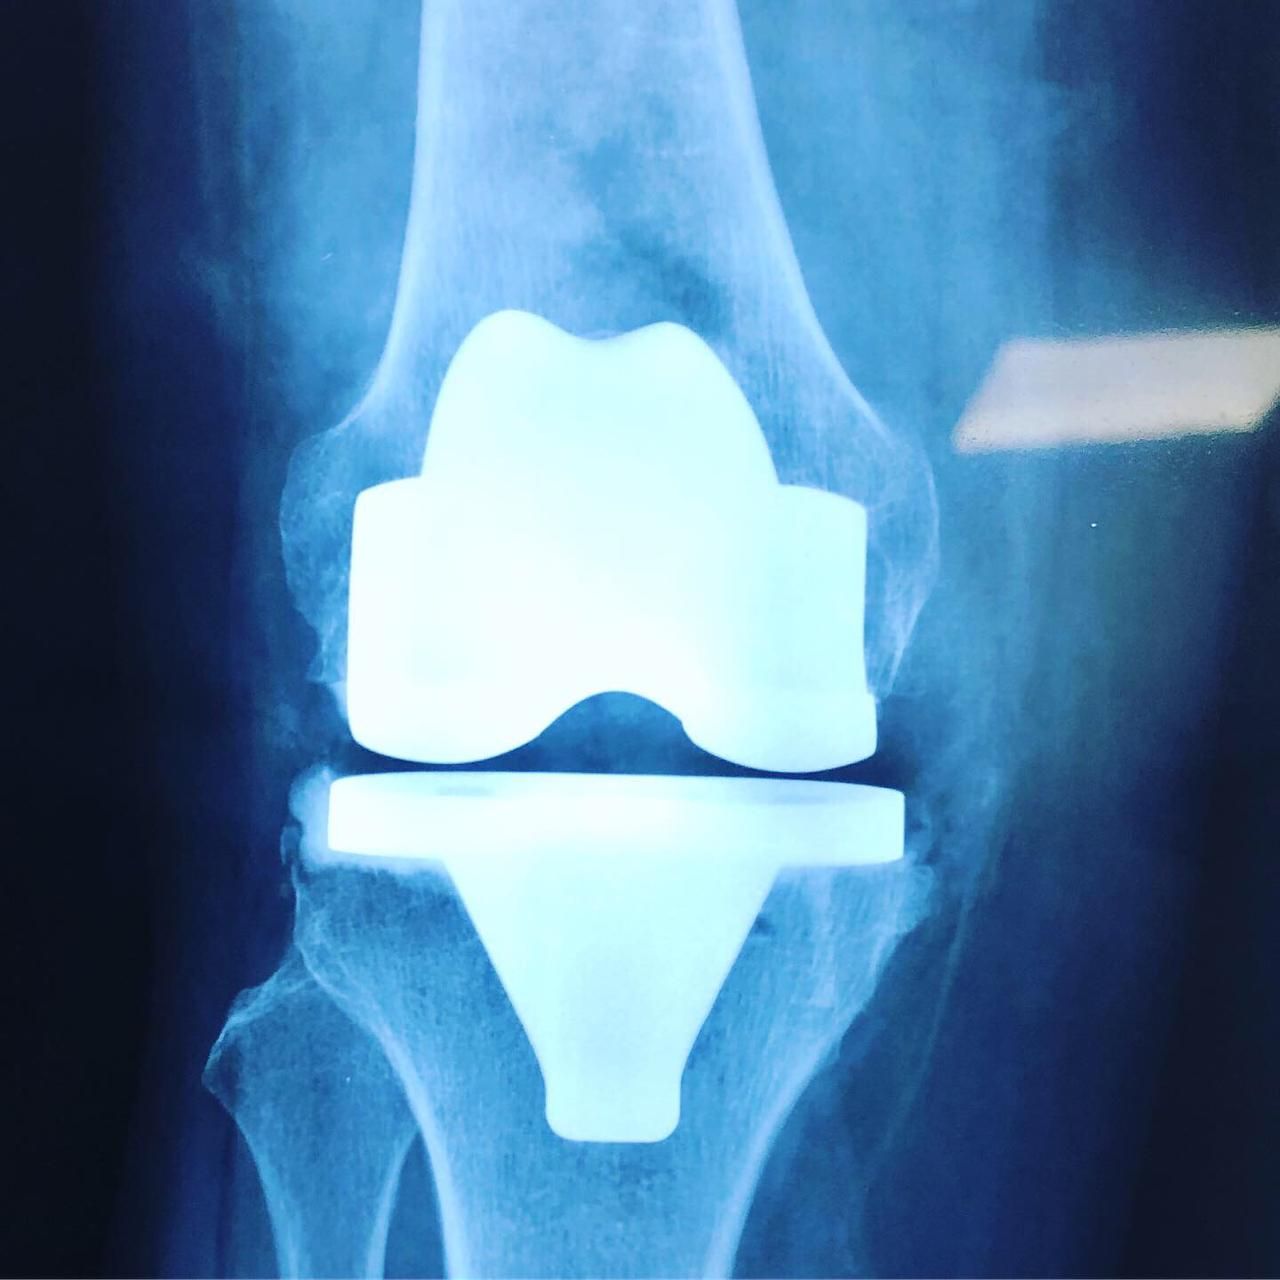

- Prótesis de rodilla

- Reconstrucción articular